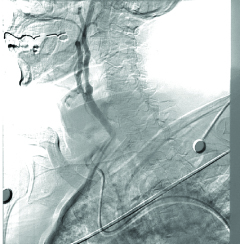

An 87-year-old man presented to the cardiology clinic for elective carotid intervention. He had a previously diagnosed history of right frontal stroke, chronic kidney disease, hypertension (HTN), chronic systolic heart failure, carotid artery disease, and peripheral artery disease. The patient presented with shortness of breath; he denied chest pain, palpitations, and muscle or joint pain. A clinical diagnosis of internal carotid artery stenosis was made, and a carotid angiogram showed 70% occlusion of the right internal carotid artery. The stenosis had reduced the blood flow and increased the risk of emboli (Figure 2). Surgery was consulted and he was considered high risk for endarterectomy due to comorbidities and age. Hence, the patient was scheduled for internal carotid artery stenting in the catheterization laboratory.

Figure 2

Figure 2. Carotid Artery Angiogram before Stenting. Right internal carotid artery stenosis reduces blood flow, which increases the risk of emboli.